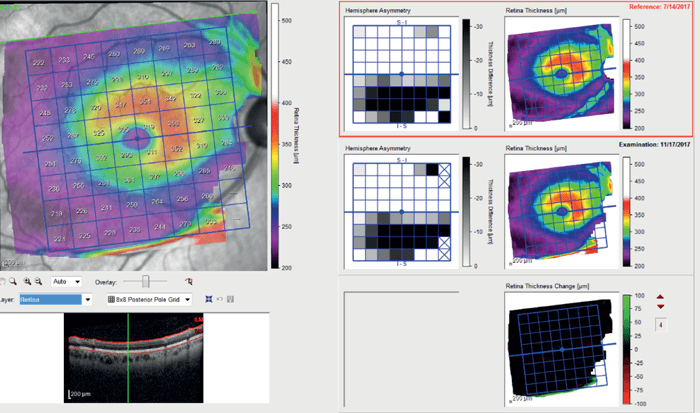

Optical Coherence Tomography Retinal Nerve Fiber Layer (OCTRNFL) with the SPECTRALIS platform (Heidelberg Engineering) revealed temporal thinning in the right eye, more in the inferotemporal quadrant (see Figure 2). Glaucoma causes retinal thinning and asymmetry in the macula (specifically in the ganglion cell layer), so we assessed OCT Macula which revealed relative asymmetry and thinning inferiorly (see Figure 3). Ganglion Cell Layer segmentation revealed generalized thinning and asymmetry between the superior and inferior hemifield.